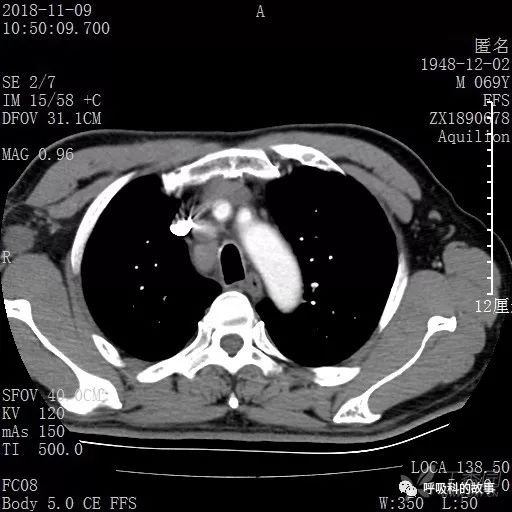

胸部增强CT示右肺门占位伴远端阻塞性肺炎,纵膈、右肺门、右侧颈根部、右侧腋下及肝门部肿大淋巴结。两侧胸腔少量积液。

纵隔窗的增强CT